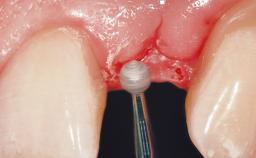

Late Placement of an Implant in a Maxillary Left Central Incisor Site

A 36-year-old female patient was referred for the replacement of the upper left central incisor (tooth 21), which had fractured. Although the tooth had been asymptomatic for many years, the crown began to loosen, at which time she presented to her dentist for an assessment. Teeth 21 and 22 had both been endodontically treated many years previously. She was a healthy individual and a non-smoker.

Soft Tissue Grafting Simultaneous

Soft Tissue Anatomy Intact Defective

Soft Tissue Contour and Volume Slightly compromised